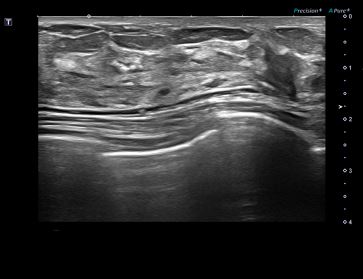

상기환자는 외부검사 이상소견으로 내원하신 40대초반 여성분으로 의심스러운 좌측 석회부위 조직검사 시행해 유방암 진단되었습니다